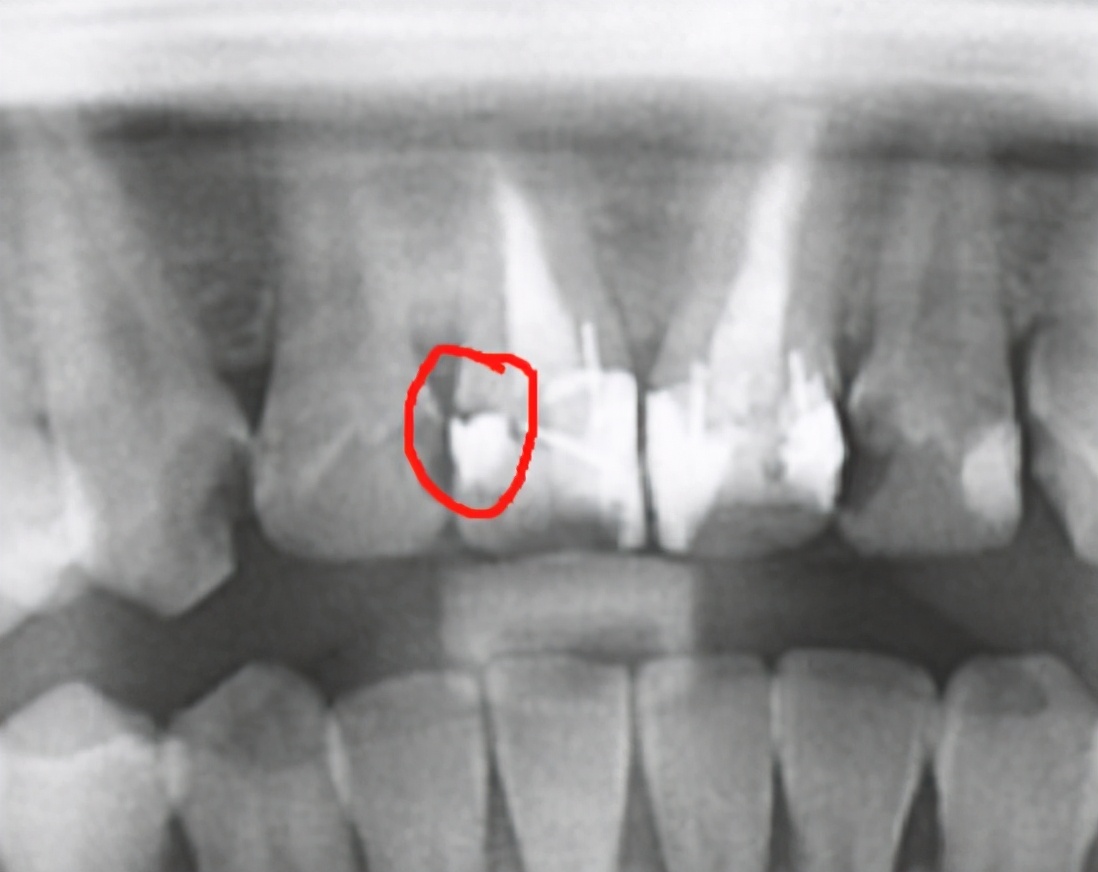

(3)邻面龋充填后敏感,可拍摄患牙区的小牙片,看看是否有相邻区域的牙齿还有未发现的龋坏,也可顺便检查一下充填物是否有悬凸或者未充填到位的地方,若有,及时处理便可解决问题。